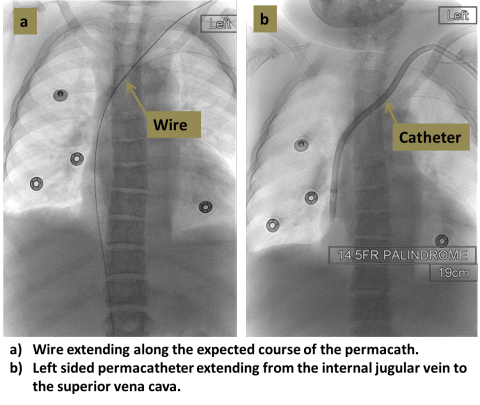

An interventional radiologist uses ultrasound to access the target vein, most commonly the internal jugular vein in the neck. X-rays are then used to guide placement of the catheter so that the tip lies in the central veins near the heart. The catheter is tunneled beneath the skin and exits the skin usually in the upper chest.